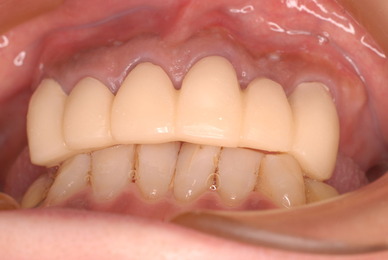

歯をいじられ体も心もボロボロになった患者さんからの手紙です。マスコミや権威などがいかにいい加減かわかります。歯は触らないほうがよろしいのです。

そもそも歯を触り何らかの金属やセラミックを入れる行為そのものが医学的には傷害処置ですから、なるべく避けるべき物なのです。